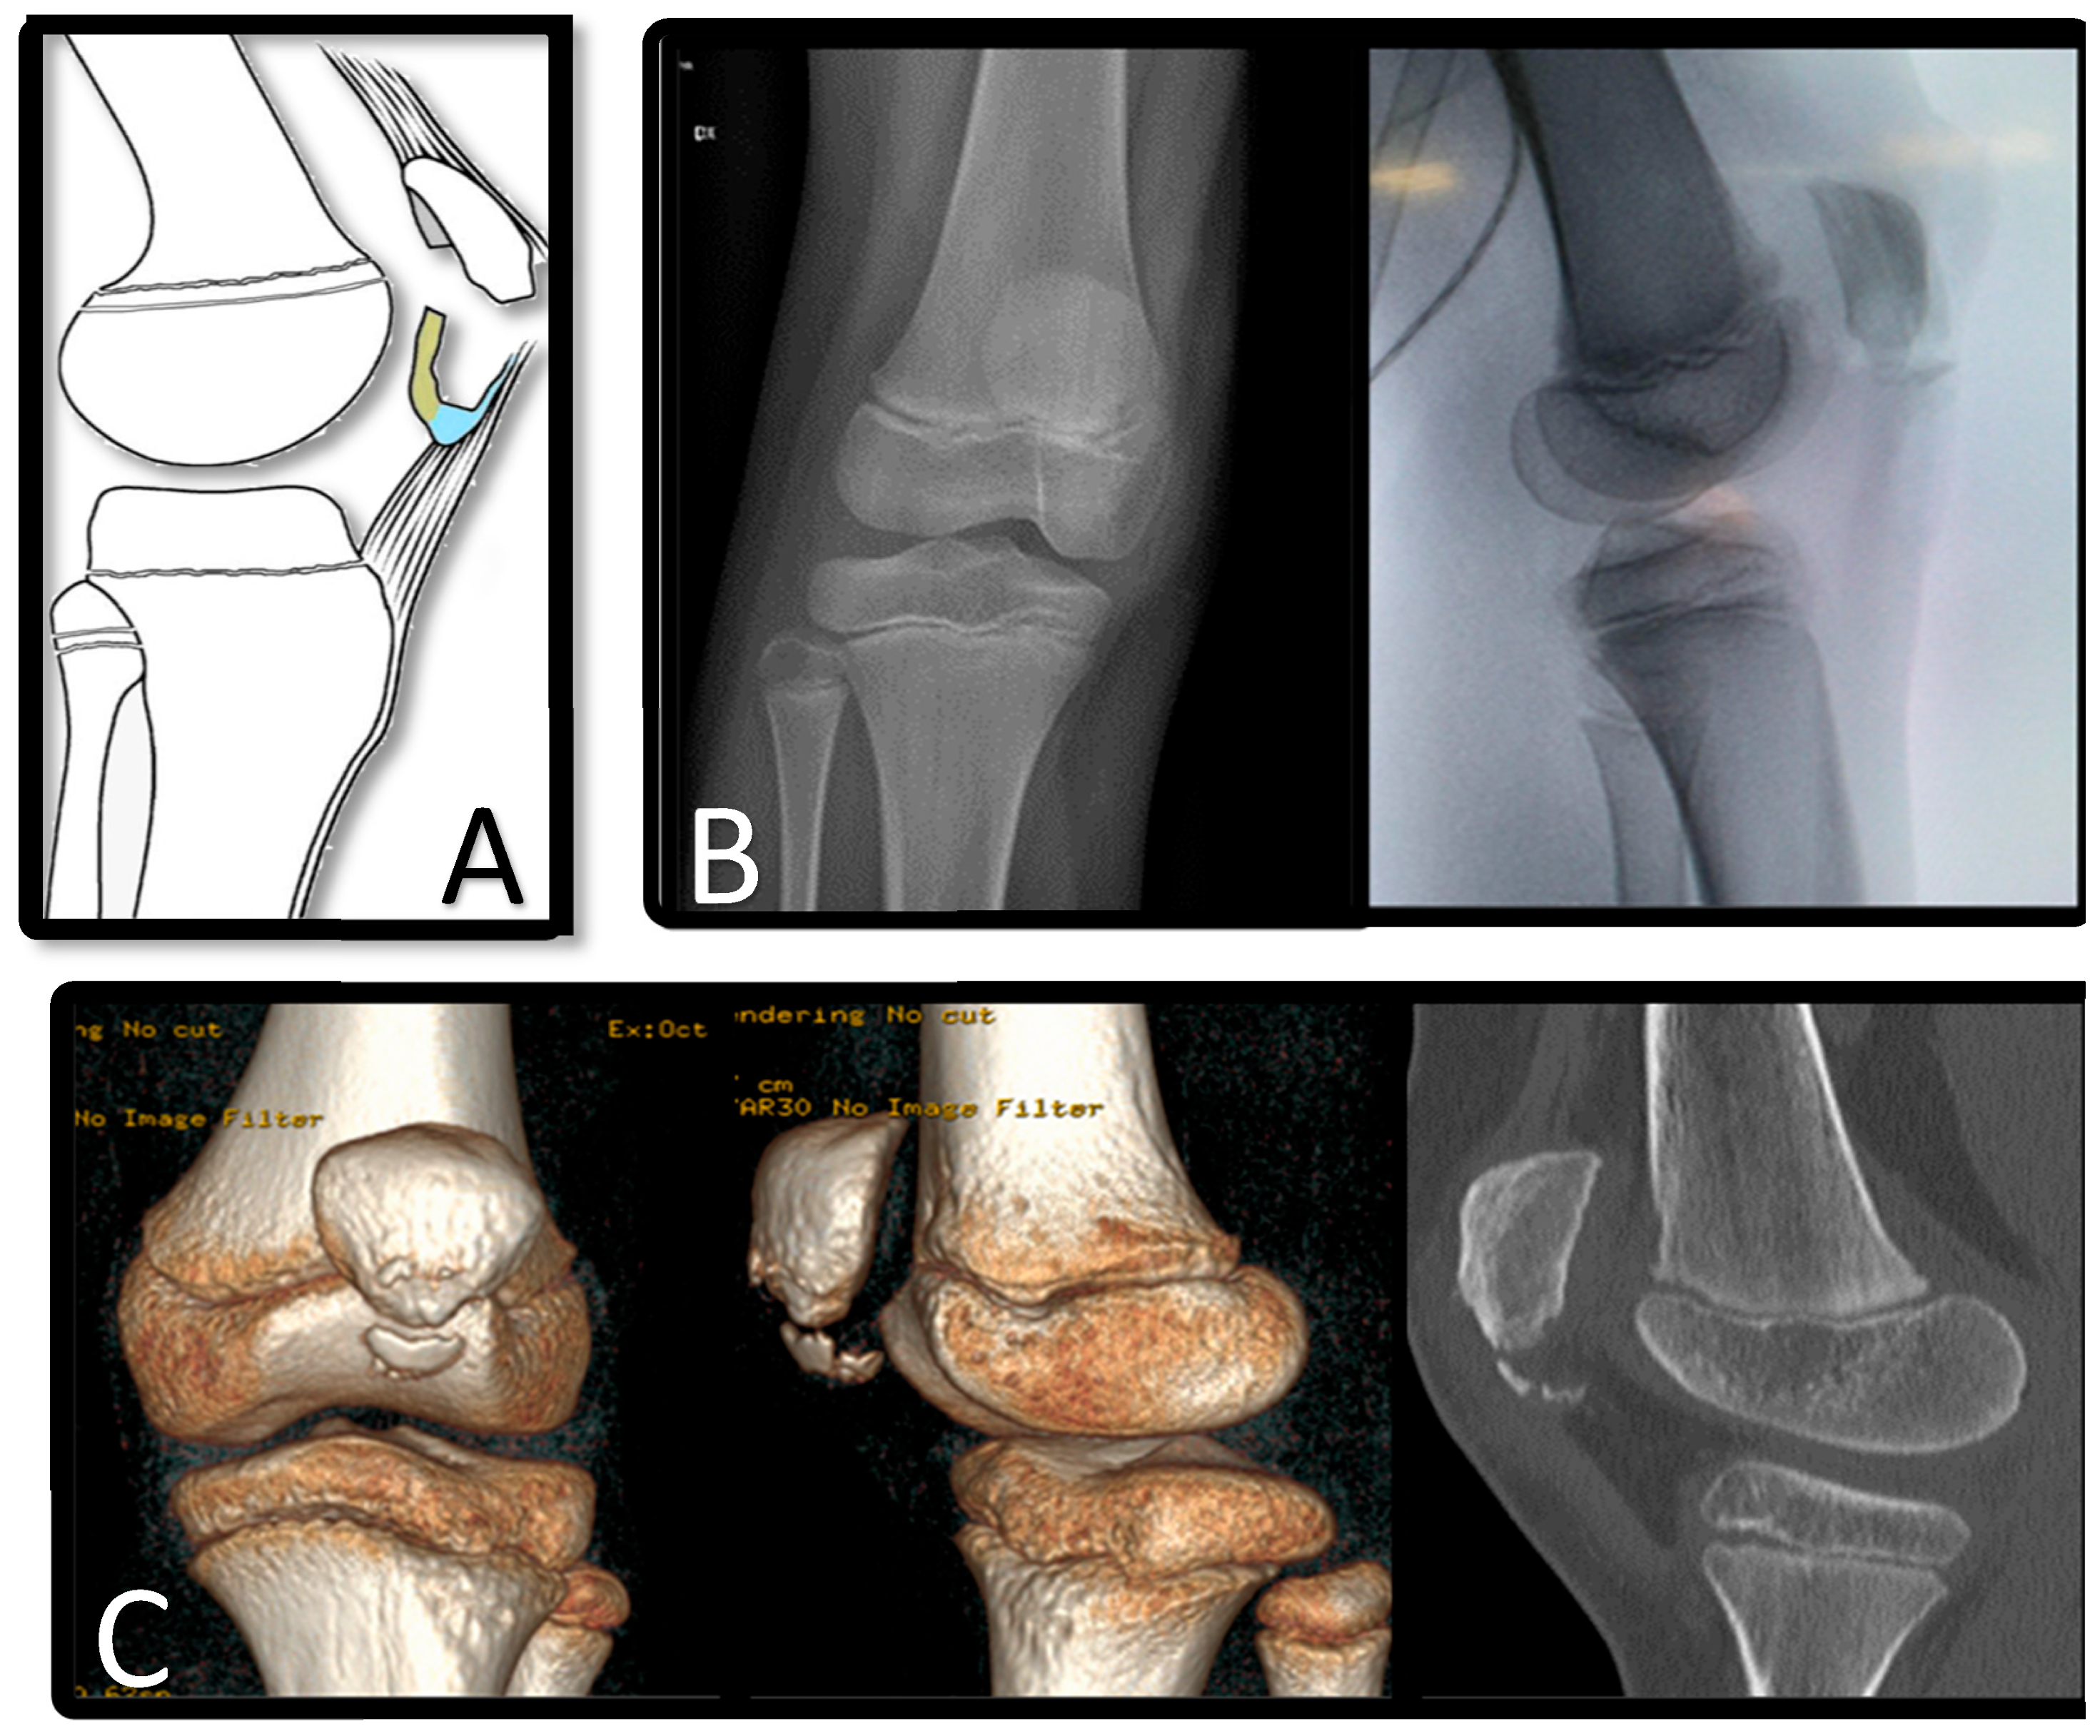

Patellar sleeve avulsion fractures are rare injuries seen in children between 8 and 12 years of age and are characterized by the separation of the cartilage “sleeve” from the ossified patella (Figure 1).

Figure 1. Representation of patellar sleeve fracture. (A): cartilage (yellow) and periosteum and cartilage (blue). (B): X-ray in antero-posterior and lateral view. (C): CT scan with 3D reconstruction.